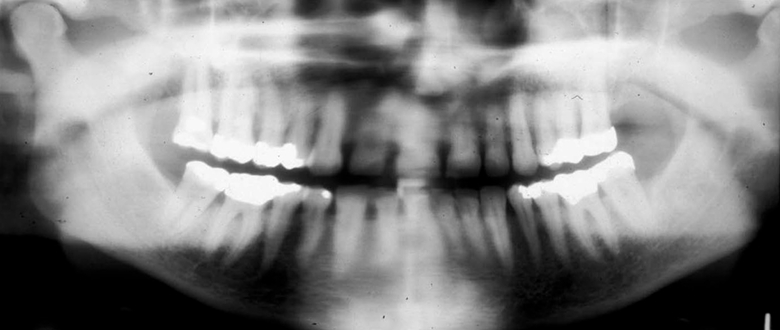

What is wrong with this image?

head turned

unequal magnification of one side; overlaped contacts on ONE side